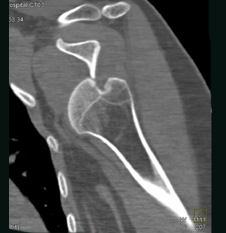

问题 男,18岁,肩部外伤,疼痛、活动受限,结合图像,最可能的诊断是 ( )

选项 A、肩锁关节脱位 B、肩关节未见脱位 C、肩关节喙突下脱位 D、肩关节锁骨下脱位 E、肩关节盂下脱位

答案 E